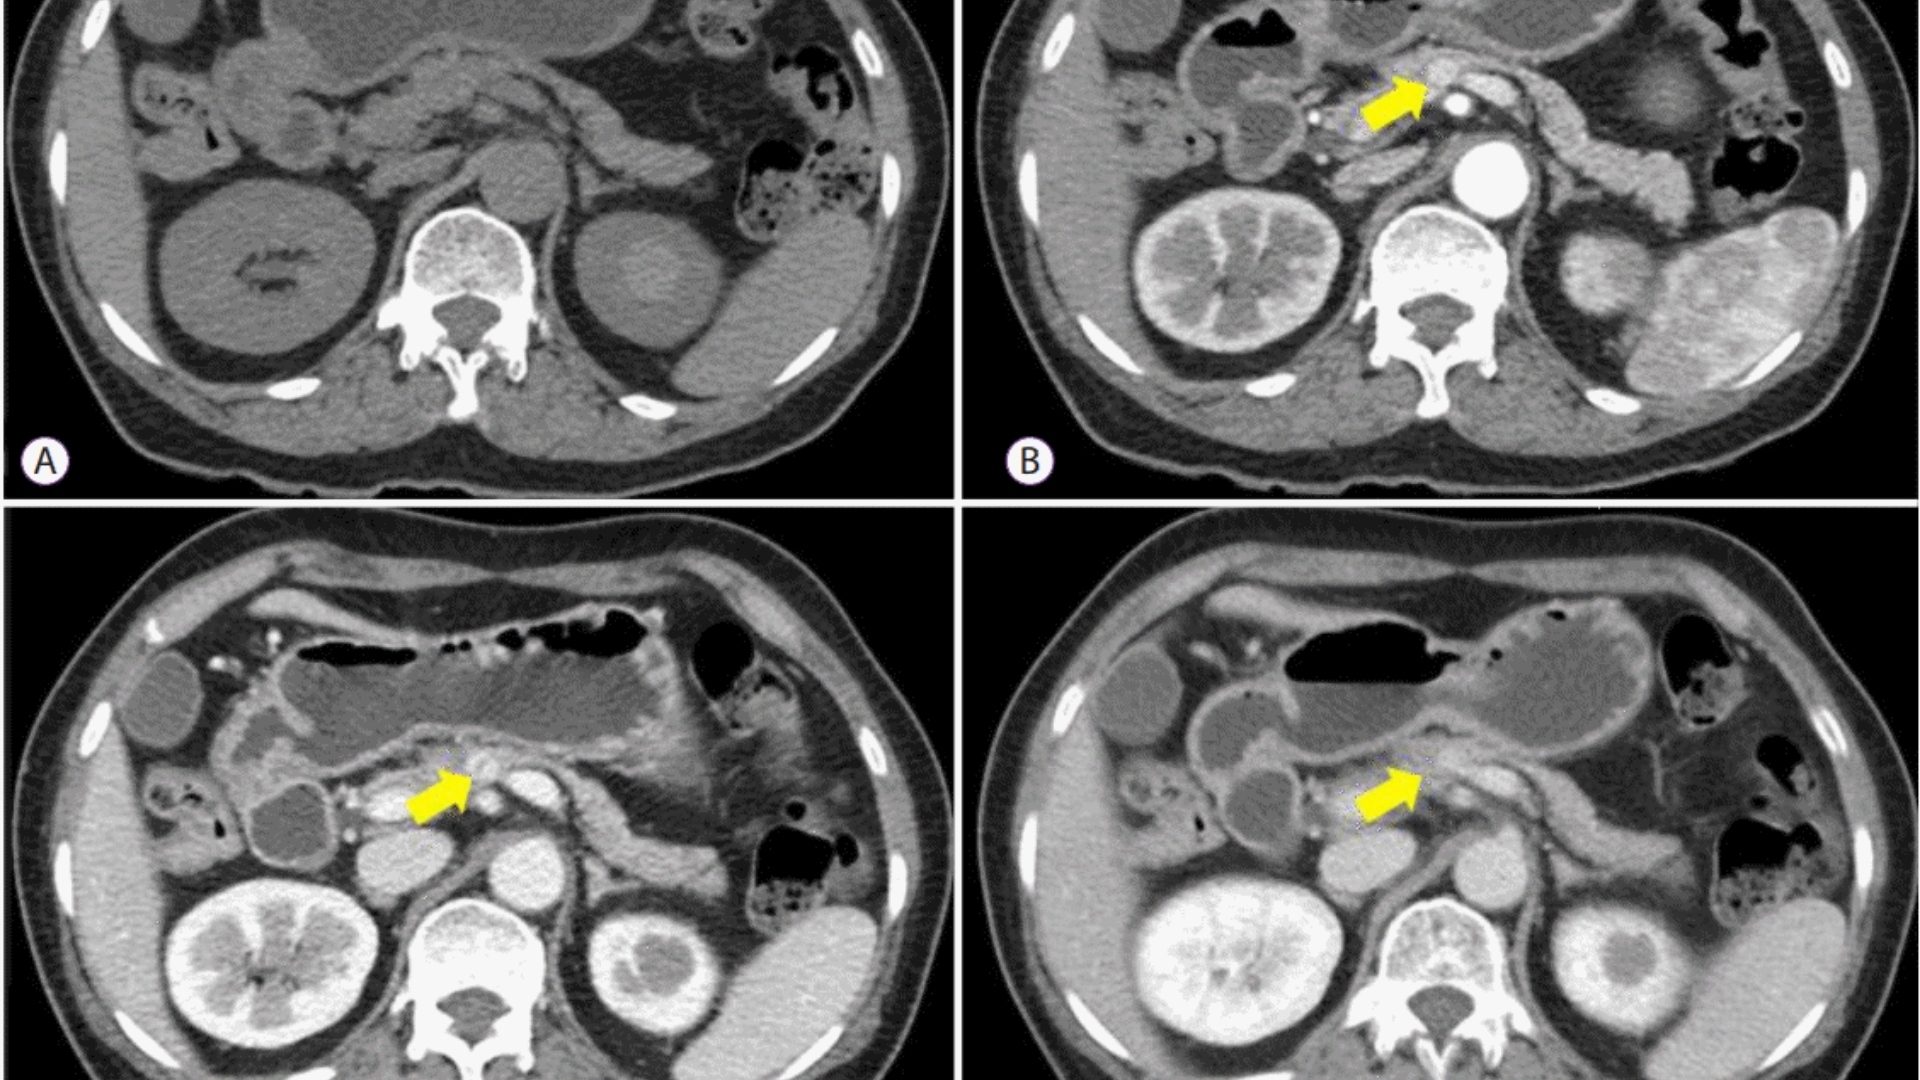

• 進階診斷:最先進的影像(例如 PET-CT、Siemens MRI)和分子剖析,以找出腫瘤的代謝漏洞。

• 醫療記錄:最近的診斷報告、影像掃描(如 CT、MRI、PET-CT)、病理結果和治療史。接受數位或實體複本。